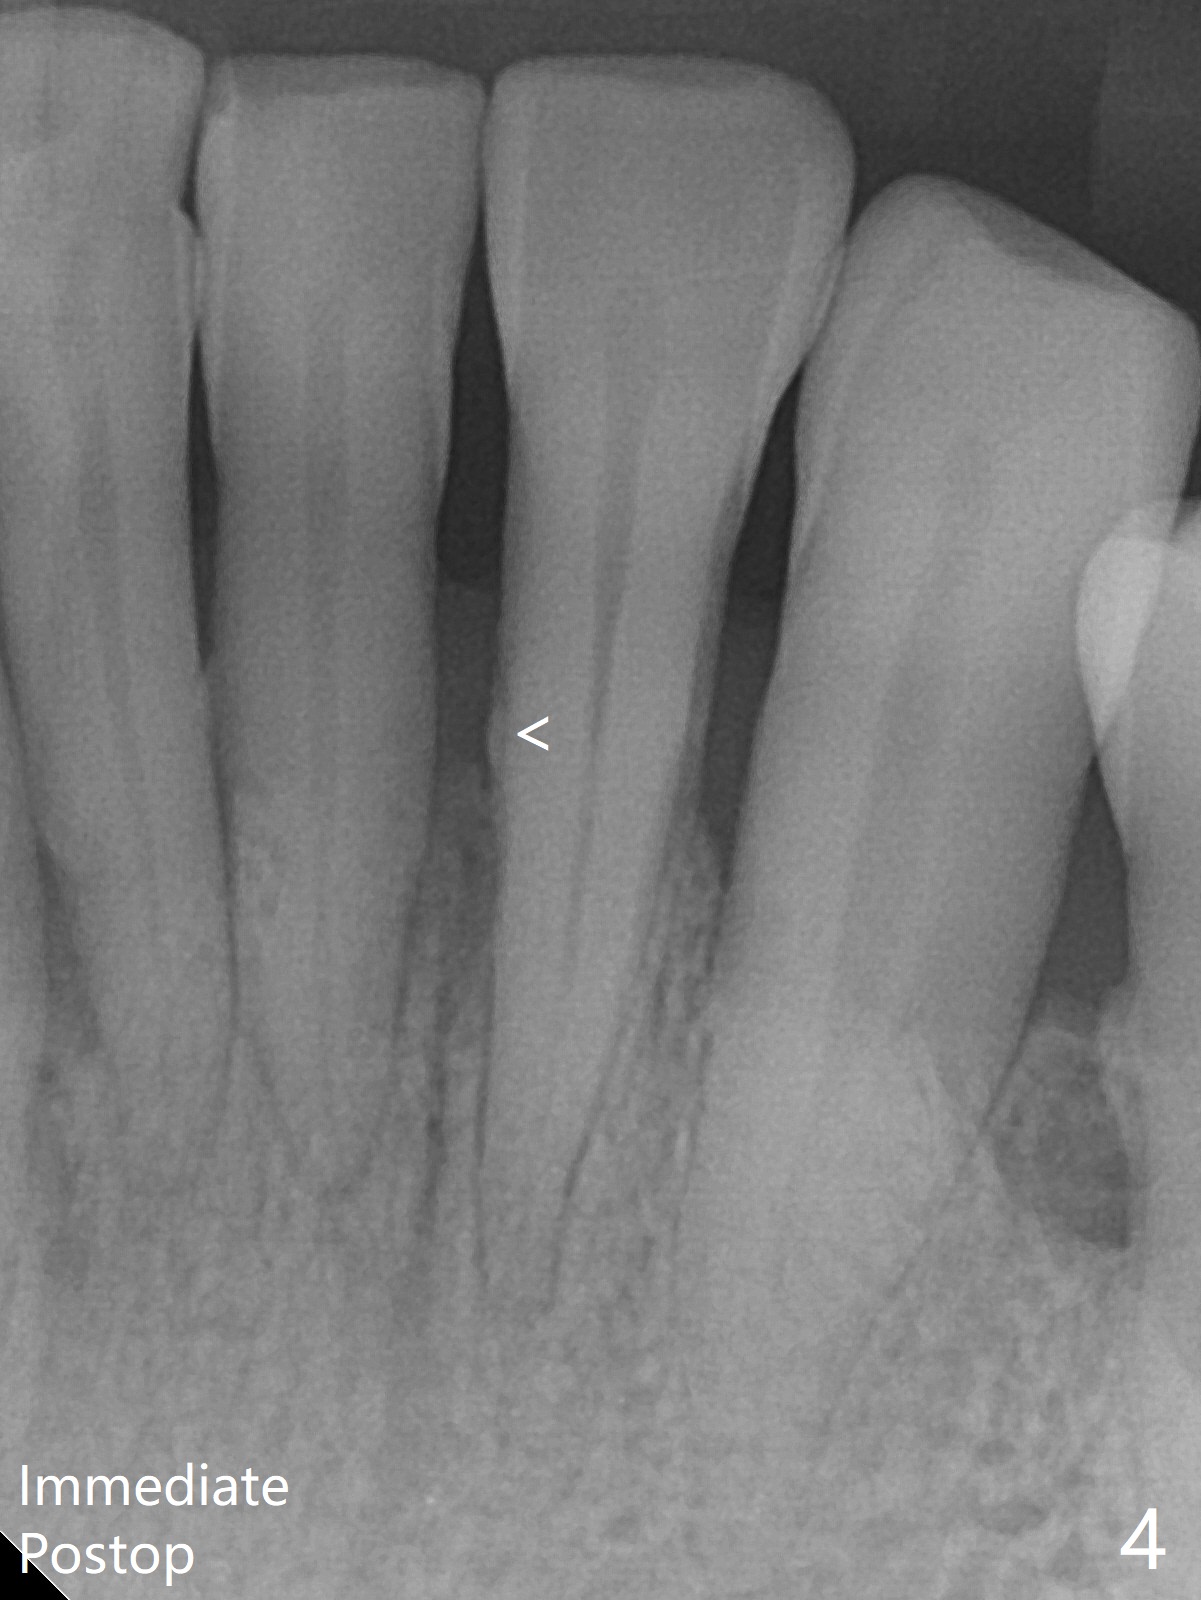

A 45-year-old woman returns for perio maintenance with erythematous and edematous papilla between #23 and 24. Two days later the infection subsides with sinus track (Fig.1 <). With infiltration anesthesia, Waterlase is used for outer and inner (steps 1,3) pocket de-epithelization (and retratction), and sulcular debridement/degranulation (step 5, Fig.3). Gingivectomy (step 2) is omitted because of severe existing gingival recession. Scaling and root planing is not conducted since step 3 seems to be able to remove fine subgingival calculus (Fig.2 <). But it appears not sufficient (Fig.4). Bone decortication should be implemented in future cases (step 6). Mepivacaine is administered in block fashion immediately postop for pain control. The patient is doing fine postop.